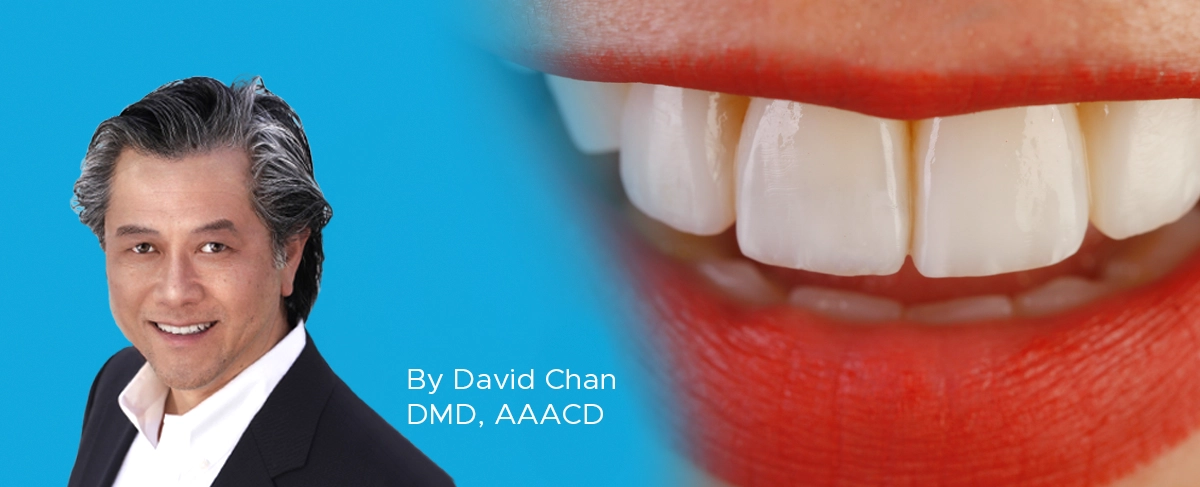

ESTHETIC EVALUATION:

Natural shade blending, translucency, and surface gloss are essential for matching the adjacent enamel boundaries. In almost all cases, it is the proper opacity of the composite resin which makes the restoration simply blend in and disappear with the native tooth structure.

These simple steps demonstrate that once the occlusal pattern and morphology has been created, the restoration can be refined very quickly to obtain the smoothness and luster of natural tooth structure, that it is visibly undetectable to the eye even at the magnification of these photos (FIG. 16, 17). The key to Evanesce Bulk Cure seamlessly blending into the remaining tooth structure lies in the fact this composite has an opacity similar to natural tooth structure. The dual-cure chemistry ensures complete polymerization, in contrast to light-cure composites which require a layered placement technique because the material opacity and cavity depth can limit polymerization.

Final restoration of tooth #28 (#44). Note the seamless blending into the remaining tooth structure and the final luster that has been achieved.